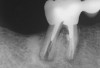

The length of the post space should be at least one half the root length while still maintaining the apical seal of gutta-percha.3,7,37 It is recommended that gutta-percha be removed using a heated endodontic instrument and/or canal-safe Gates-Glidden drills. Aggressive use of inflexible post drills within the root canal can lead to perforation of the canal with subsequent negative consequences on the survivability of the tooth (Figure 2).3,7 This author recommends that the post drills provided by manufacturers be used more as a canal-sizing instrument than for post preparation within the canal. The rationale for using the post drill in this manner assures that the root canal is not overprepared with the potential of perforation of the root canal. It is important when removing the gutta-percha that the length of the root canal be known so that whichever technique is used to remove the gutta-percha, the instrument can be marked to the length of root canal preparation desired. In the case of a rotary instrument or a heated instrument, an endodontic stopper can be placed on the instrument to the length desired (Figure 3). After making the post space, it is advisable to make a radiograph of that tooth to verify the length of the post space and the removal of the gutta-percha (Figure 4).

Figure 4  Take verifying radiographs to check on gutta- percha removal and length of post space desired.

Figure 4